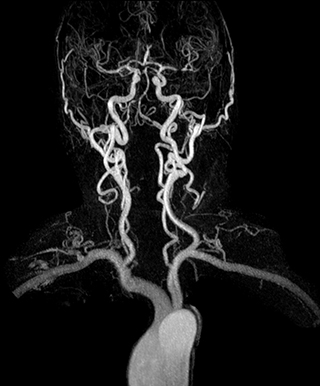

3D dynamic MRA of head and neck

Excellent image quality is obtained in this dynamic scan., C-SENSE factor 5.4, scan time is 1:20 min, voxel size is 0.8 x 0.8 x 1.6 mm, Ingenia Ambition, 1.5T.

Dynamic MRA of head and neck

Cor 3D T2